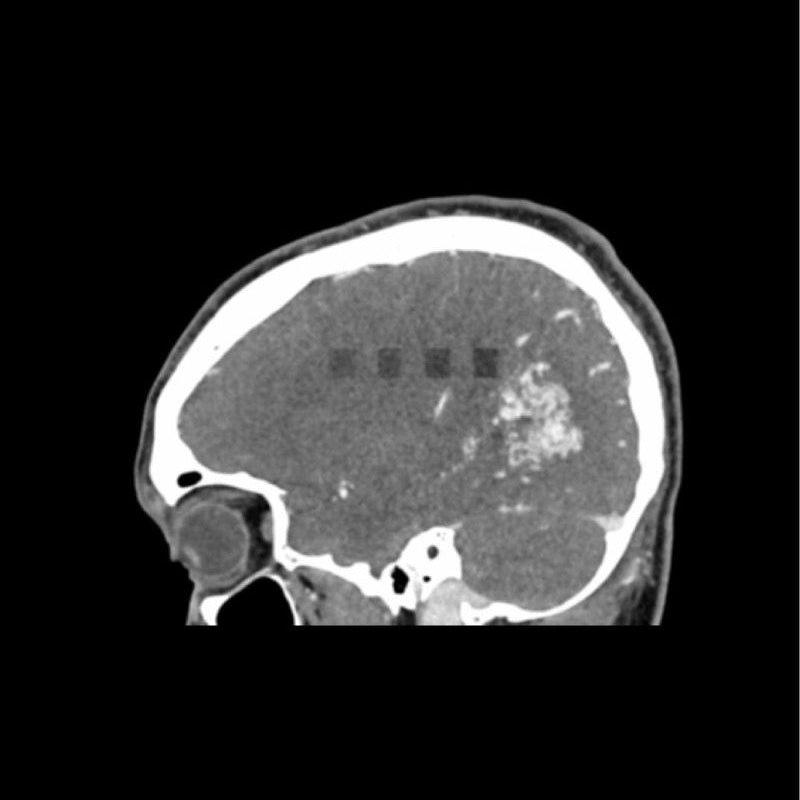

This phantom simulates a contrast medium enhanced head in arterial phase (CT angiography). It covers the vertex to the foramen magnum. The phantom has 10 low-contrast lesions in the centrum semiovale and the right hemisphere has an arteriovenous malformation.

The phantom can be used in CT (including CBCT) to evaluate and optimize imaging performance and AI-enabled diagnosis. It is also suited for training purposes. The phantom provides a detailed and realistic simulation of vascular structures, soft and bone tissue. Air voids are filled with a cellulose-polymer composite of approx. -160 HU.

- Arteriovenous malformation of the right hemisphere.

- 5 rod-shaped lesions on each side in the centrum semiovale at the periventricular and supraventricular level.

Lesion diameter: 10 mm

Lesion height: 10.5 mm

Lesion contrast: Approx. -60 to -20 and 20 to 60 HU at 120 kVp